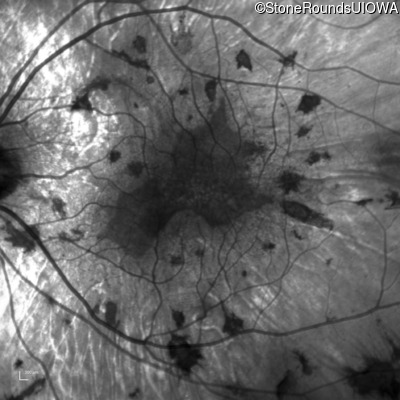

Infrared Fundus Photograph - Left - 20/25 +1

Exemplar